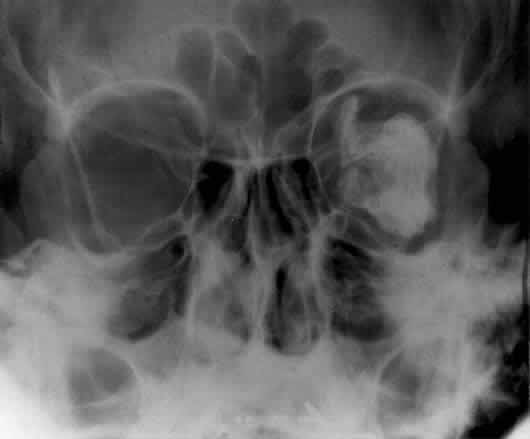

Calcification in the orbit can be seen in retinoblastoma, meningioma, organized hematoma, or a phlebolith associated with venous malformations. Intraocular calcification is seen with tumors such as retinoblastoma or with degenerative changes of the lens, choroid, or vitreous23 (Figs. 10 and 11).

Fig. 10. Caldwell projection of a hemangioma of the left orbit. Soft tissue density is seen in the lateral orbit with partial calcification (arrows).

Fig. 11. A phthisis bulbi globe with calcification of the choroid and sclera. Note the outline of the globe and the location within the orbit. Calcification of the globe can occur with degenerative changes of the eye.